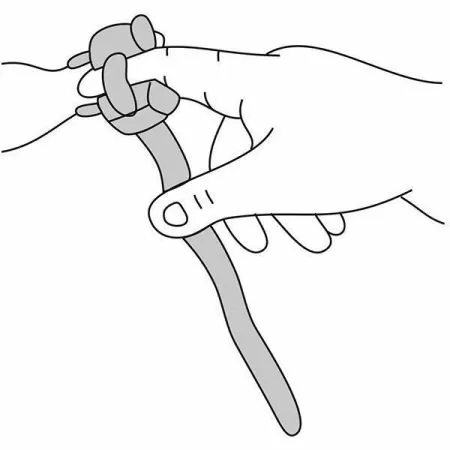

- Датчик пульсоксиметрический «Манжетка» состоит из Y-образной пары излучатель-фотоприемник и фиксирующего ремешка. Поместите излучатель и фотоприемник в разъемы фиксирующего ремешка и закрепите на пациенте.

- При этом следует следить, чтобы излучатель находился напротив фотоприемника и фотоприемник прилегал к мягким тканям.

- Не затягивайте датчик слишком сильно, чтобы не нарушить циркуляцию крови.